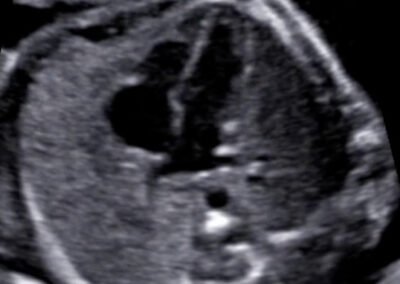

Genetický ultrazvuk Fetální echokardiografie Dopplerovské vyšetření krevního oběhu miminka a placenty Screening předčasného porodu Screening preeklampsie a zaostávání růstu miminka Vyšetření vícečetných těhotenství 3D-4D ultrazvuk Určení pohlaví miminka